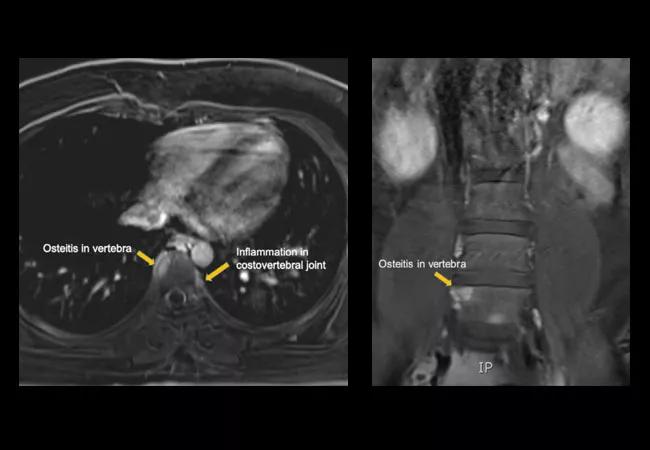

His chest wall exam was normal, but he mentioned a years-long history of severe, refractory body acne that presented on his back, chest wall and groin, consistent with nodulocystic acne and hidradenitis suppurativa. His bloodwork showed systemic inflammation, with leukocytosis, neutrophil predominance and markedly elevated erythrocyte sedimentation rate (ESR). Magnetic resonance imaging (MRI) of the chest wall and spine revealed multiple areas of contrast enhancement in the sternum, multiple costovertebral joints and multiple vertebrae, findings consistent with osteitis.

Osteitis and Acne: SAPHO Syndrome